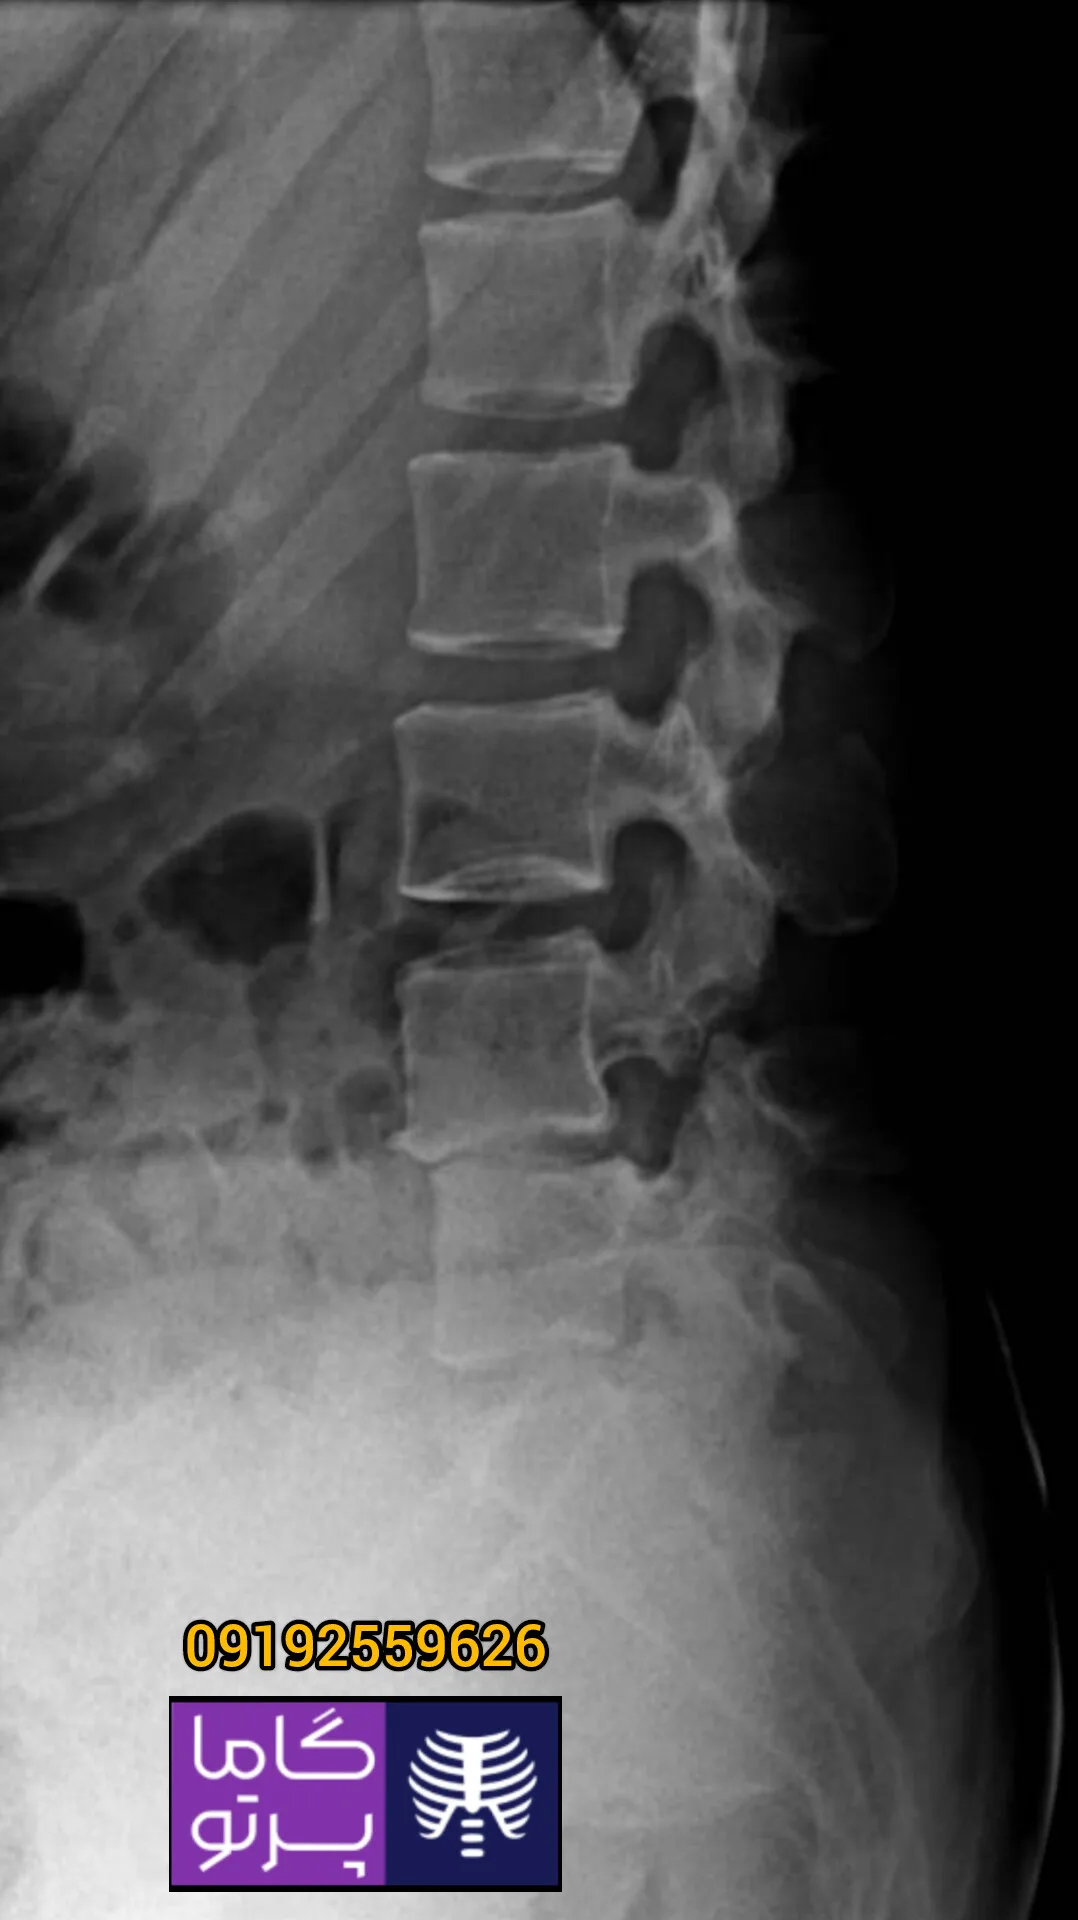

تصاویری از رادیولوژی در منزل توسط گاما پرتو

در این روش تصویر برداری یک صفحه (گیرنده یا دتکتور) در زیر عضو و قسمت مورد نظر قرار داده می شود و اشعه ایکس(دُز از اشعه جهت تشخیص) به همان قسمت که روی صفحه قرار گرفته تابنده می شود و توسط صفحه اطلاعات دریافت می شوند و همین اطلاعات پس از پردازش های لازم در نهایت عکس رادیولوژی به ما ارائه می دهد. کاربردهای رادیولوژی در منزل دقیقاً همان کاربرد رادیولوژی در بیمارستان ها می باشد از جمله بررسی انواع شکستگی ها، دررفتگی مفاصل، آرتروز مفاصل، دیدن پروتز های داخل استخوان از نظر بررسی موقعیت پروتز، آب آوردگی ریه(اِدم وافیوژن) و عفونت ریه، شکستگی دنده ها، انساد و وجود هوا در شکم و… می باشند. رادیولوژی در منزل تمام این خدمات را ارائه می دهد.